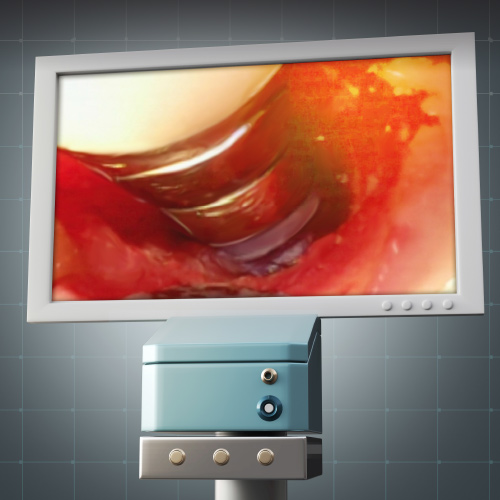

The Dental Videoscope: Improved Outcomes With Minimally Invasive Periodontal and Peri-Implant Surgery

This Compendium eBook features a continuing education (CE) article that reviews the use of the videoscope for videoscope-assisted minimally invasive surgery for teeth and implants.